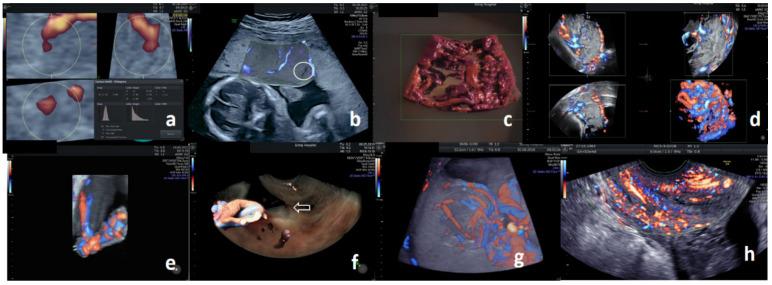

Realistic reconstruction of angioarchitecture within the morphological landmark with three-dimensional sonoangiography (three-dimensional power Doppler; 3D PD) may augment standard prenatal ultrasound and Doppler assessments. This study aimed to (a) present a technical overview, (b) determine additional advantages, (c) identify current challenges, and (d) predict trajectories of 3D PD for prenatal assessments. PubMed and Scopus databases for the last decade were searched. Although 307 publications addressed our objectives, their heterogeneity was too broad for statistical analyses. Important findings are therefore presented in descriptive format and supplemented with the authors' 3D PD images. Acquisition, analysis, and display techniques need to be personalized to improve the quality of flow-volume data. While 3D PD indices of the first-trimester placenta may improve the prediction of preeclampsia, research is needed to standardize the measurement protocol. In highly experienced hands, the unique 3D PD findings improve the diagnostic accuracy of placenta accreta spectrum. A lack of quality assurance is the central challenge to incorporating 3D PD in prenatal care. Machine learning may broaden clinical translations of prenatal 3D PD. Due to its operator dependency, 3D PD has low reproducibility. Until standardization and quality assurance protocols are established, its use as a stand-alone clinical or research tool cannot be recommended.

通过三维超声血管造影术(三维能量多普勒;3D PD)在形态学标志内对血管构筑进行逼真重建,可能会增强标准的产前超声和多普勒评估。本研究旨在(a)提供技术概述,(b)确定额外优势,(c)识别当前挑战,以及(d)预测3D PD在产前评估中的发展轨迹。检索了过去十年的PubMed和Scopus数据库。尽管有307篇出版物涉及我们的目标,但它们的异质性太大,无法进行统计分析。因此,重要发现以描述性形式呈现,并辅以作者的3D PD图像。采集、分析和显示技术需要个性化,以提高血流容积数据的质量。虽然孕早期胎盘的3D PD指标可能会改善子痫前期的预测,但需要进行研究以规范测量方案。在经验丰富的人员操作下,独特的3D PD发现可提高胎盘植入谱系的诊断准确性。缺乏质量保证是将3D PD纳入产前护理的核心挑战。机器学习可能会拓宽产前3D PD的临床应用。由于其对操作者的依赖性,3D PD的可重复性较低。在建立标准化和质量保证方案之前,不建议将其作为独立的临床或研究工具使用。